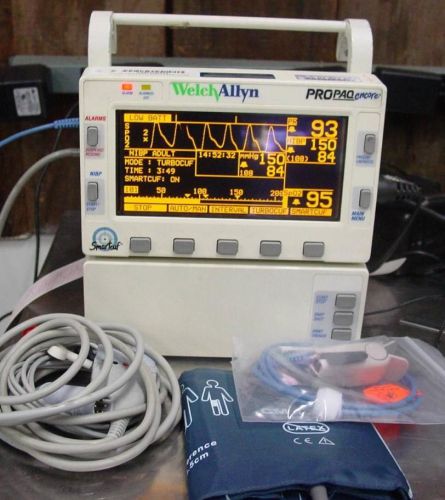

Welch Allyn PROPAQ ENCORE 206 EL TRANSPORT MONITOR NIBP Spo2 EKG PRINTER